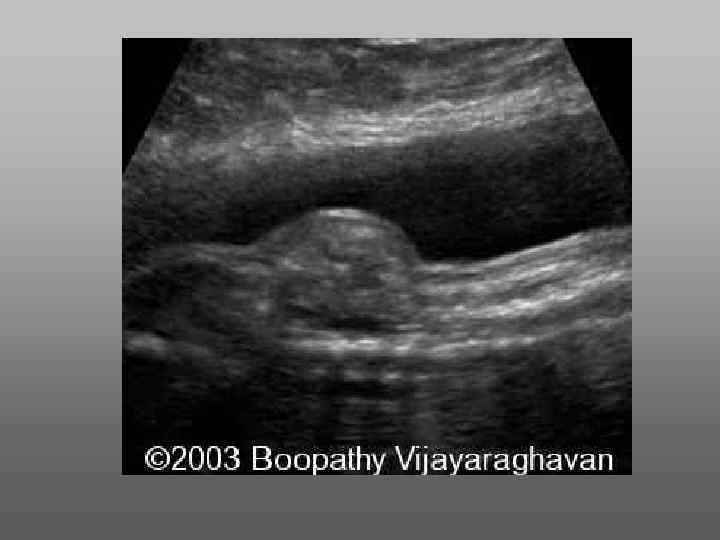

Грыжи мозговых структур можно выявить при продольном сканировании